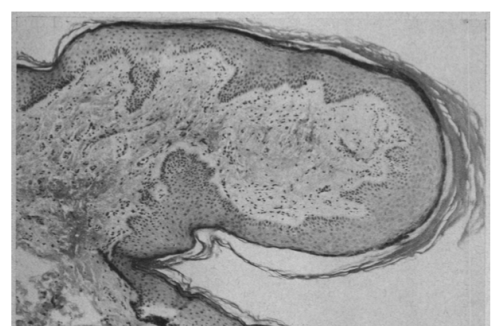

The accompanying figure compares histological sections through the penile spines of mice and chimps, and a penile papule in humans.

In contrast, a PPP in humans consists of a larger out-pocketing of the entire skin, without local layering of the keratinized epidermis to make hook-like projections, and with the bulk of the overall structure consisting of a dense, well vascularized core of connective tissue cells, rather than epithelial cells (bottom row).

Unlike the keratinized spines shown above, the papules that form in some humans are outpockets of the entire skin surface, with a dense and vascularized connective tissue core making up the bulk of the projection. Although mouse and chimp penile spines are closely associated with neural sensory receptors, human PPP are not enriched in neural structures (see Glicksman and Freeman (1966) Arch Derm 93: 56-59).

The different structure of a human penile papule